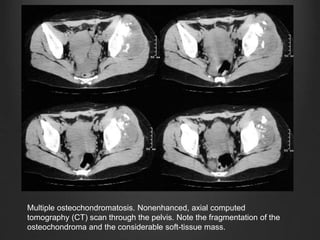

C.T. SCAN

• Allows optimal demonstration of the pathognomonic cortical

and medullary continuity of the lesion and parent bone

• Mineralization in the cartilage cap allows a correct CT

measurement

• However, it can be very difficult to correctly measure the

thickness of a totally nonmineralized cartilage cap because it

cannot be easily differentiated from surrounding muscle or

bursa.

• Cartilage cap thickness greater than 1 to 2 cm in adults and 2

to 3 cm in growing children suggests malignant

transformation

Multiple osteochondromatosis. Nonenhanced, axial computed

tomography (CT) scan through the pelvis. Note the fragmentation of the

osteochondroma and the considerable soft-tissue mass.